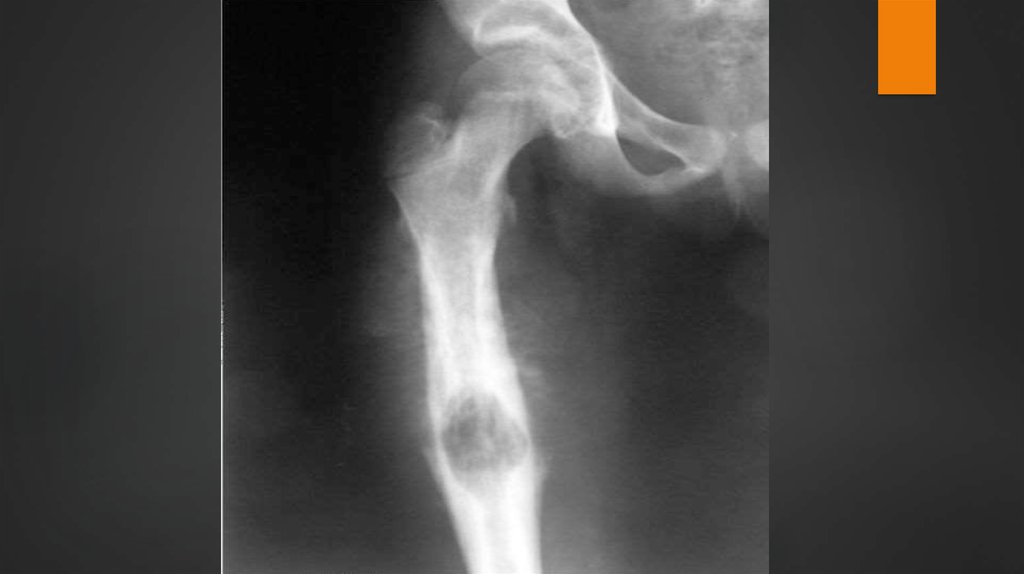

Остеобластическая остеогенная саркома

выглядит в виде интенсивного затемнения,

заслоняющего область деструкции за счёт

повышенной способности клеток опухоли

продуцировать костное вещество, в мягких

тканях нередко выявляют первичную

обызвествлённую опухоль, а также идущие

цепочкой вдоль кости обызвествлённые

лимфатические узлы.